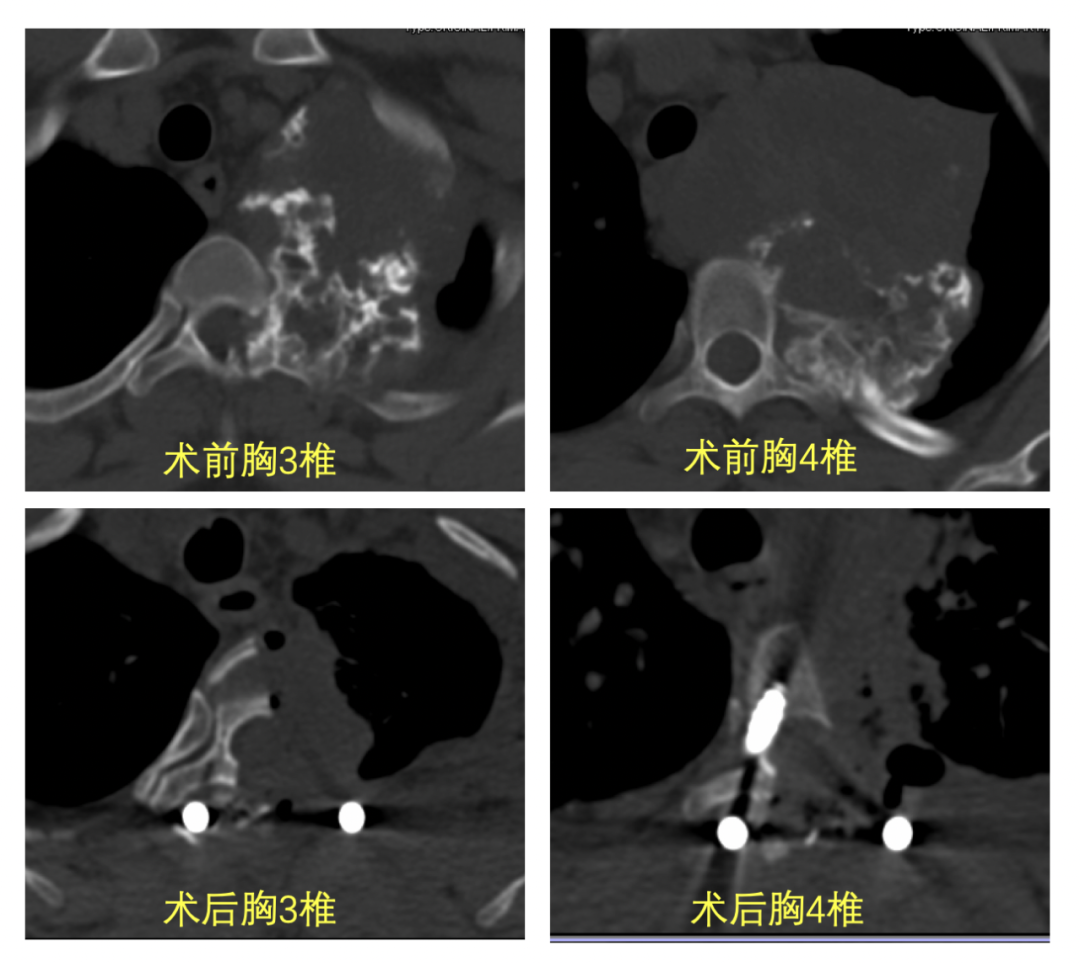

江女士转入重症监护室继续治疗,术后第一天便拔除气管插管,顺利转回胸外科病房,术后引流管顺利拔出;术后第二天便佩戴支具起床活动,复查胸部CT显示肿瘤切除完整、内固定位置良好,无继发肺部感染及其他并发症。